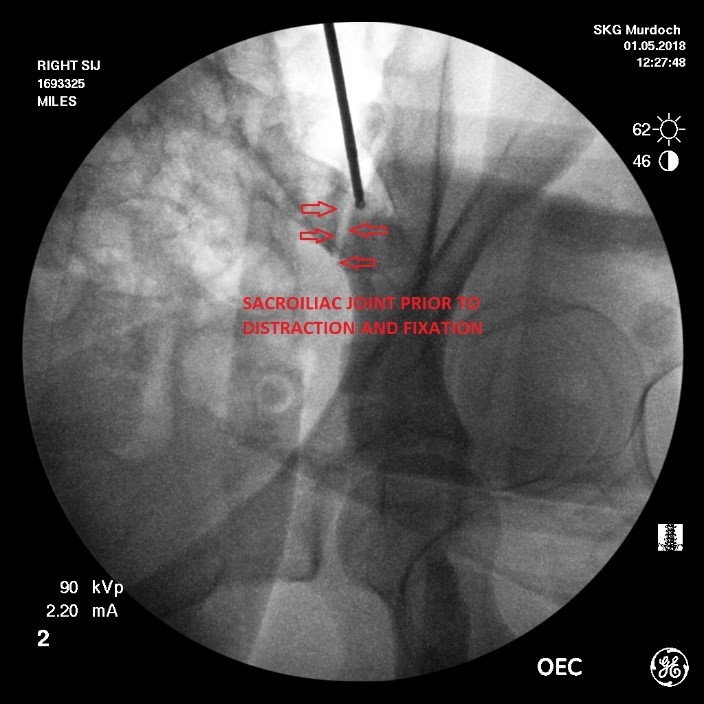

2 & 3. Distraction and fixation of the sacroiliac joint –the sacroiliac joint is indirectly distracted by distracting the medial (sacral) and lateral (iliac) boundaries of the sacral recess. To achieve this a guide pin is implanted using fluoroscopic control into the iliac bone of the pelvis. Positioning and trajectory of the guide pin is an essential component of the procedure and requires careful interpretation of fluoroscopic images performed in the antero-posterior (forward-backward), lateral and oblique planes.

Once the guide pin is positioned correctly and confirmed on the 3 fluoroscopic views, the sacral recess is progressively distracted using a series of progressively larger helical instruments until an appropriate degree of distraction of both the sacral recess and indirectly the underlying sacroiliac joint is achieved.

Once a satisfactory degree of distraction of the sacroiliac joint has been achieved, fixation of the distraction must then be obtained. This is achieved by implanting a DIANA screw sized to match the distraction obtained with the helical instruments.